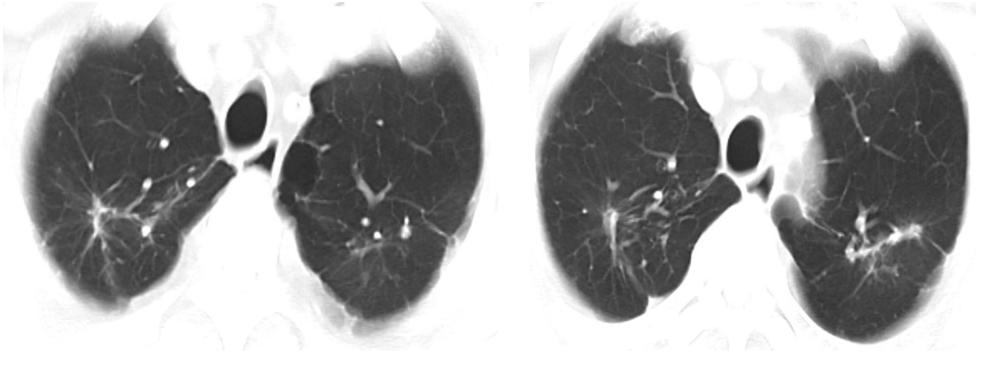

胸部CT:两肺上叶纤维条索灶及钙化灶。两肺上叶气肿伴肺大泡,左肺下叶结节,主动脉及冠脉硬化(图2)。

图2 入院时胸部CT